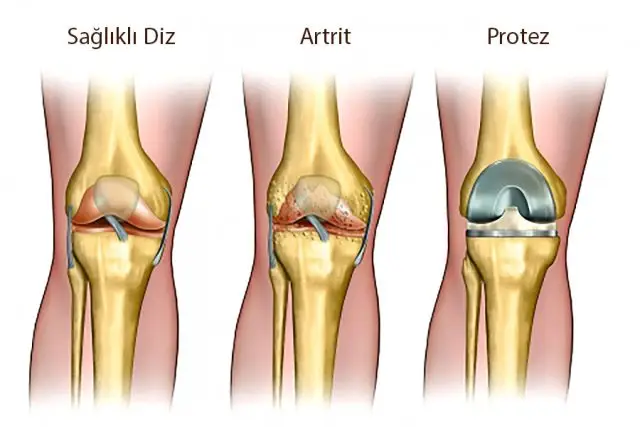

Total Eklem Değiştirme Cerrahisi Nedir?

Total eklem değiştirme cerrahisi, diğer adıyla eklem protezi ameliyatı, ileri derecede kalça veya diz ağrısı yaşayan hastalarda uygulanan en etkili tedavi yöntemlerinden biridir. Bu ameliyatın temel amacı; eklemdeki hasarlı veya aşınmış yüzeyleri yapay implantlarla değiştirerek, ağrıyı azaltmak, hareket kabiliyetini geri kazandırmak ve yaşam kalitesini artırmaktır. Eklemdeki kıkırdak doku yıllar içinde